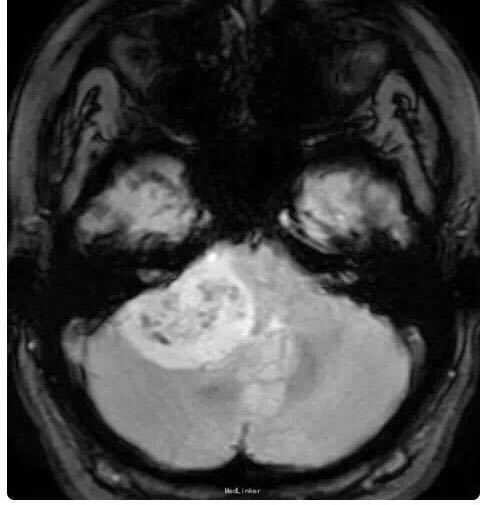

女性患者,34 岁,主因头痛、右耳听力损害以及平衡障碍 3 个月入院。

行头颅影像学检查、轴位 T1 像、轴位增强后 T1 像、冠状位增强后 T1 像以及轴位 T2 像:显示在右侧桥脑小脑角部位有一边界清楚病灶,T1 为低信号,T2 为高信号,并且伴有强化;病灶扩展至右侧颈静脉孔区,导致颈静脉孔增宽,脑干、第四脑室和小脑变形。右侧内耳道正常,病灶无颅外扩展。轴位 T2 加权 GRE 成像显示多发性病灶内出血:

诊断为颈静脉孔区神经鞘瘤。 手术切除辅助以立体定向放疗。